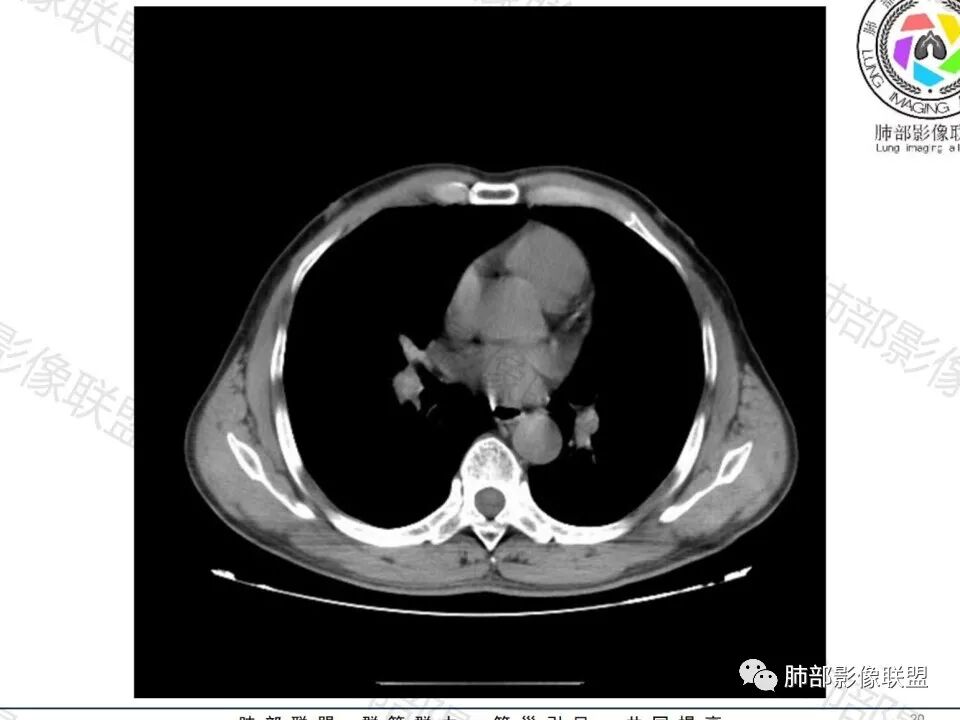

病史:男,60岁,体检左下肺结节,肿标阴性;

影像:轻微肺气肿,可能抽烟;旁边有个卫星灶4-5个,厚层无血管弯,薄层叶间裂轻度增厚,有囊腔,内侧有一个微血管,弯,另有两个微血管直,膨隆,增强血管不弯,糊墙,好像边界有些模糊,17-47-47,冠位轻度叶间裂弯。

诊断:警惕良性,隐球菌感染?

老年男性,无症状,肺气肿背景

这个囊可靠吗?

这应该是附近的肺气肿

血管进去还是比较自然

南边:

类圆形,边缘稍平直,周围晕中细微毛刺,密度均匀,均匀强化,血管走形自然,稍牵拉扭曲,支气管在近端堵塞

多发类似结节

常规思路:

1、炎性结节,多发,类似,晕,隐球菌?

2、恶性:多发:转移瘤?肺癌并多发转移瘤?